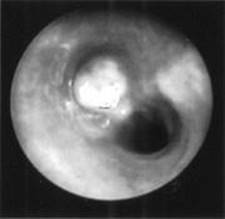

FIGURE 12-6. Radiograph of lateral soft tissue of the neck demonstrates a foreign body (nail) in the pharynx.

(Courtesy of Dr. Gregory J. Schears.)

FIGURE 12-7. Foreign body (peanut) in the right mainstem bronchus visualized by bronchoscopy.

Foreign bodies tend to lodge most commonly in the right mainstem bronchus due to the larger anatomic angle that makes traveling down right mainstem easier. (Courtesy of Dr. Gregory J. Schears.)

Direct bronchoscopic visualization (Figure 12-7).